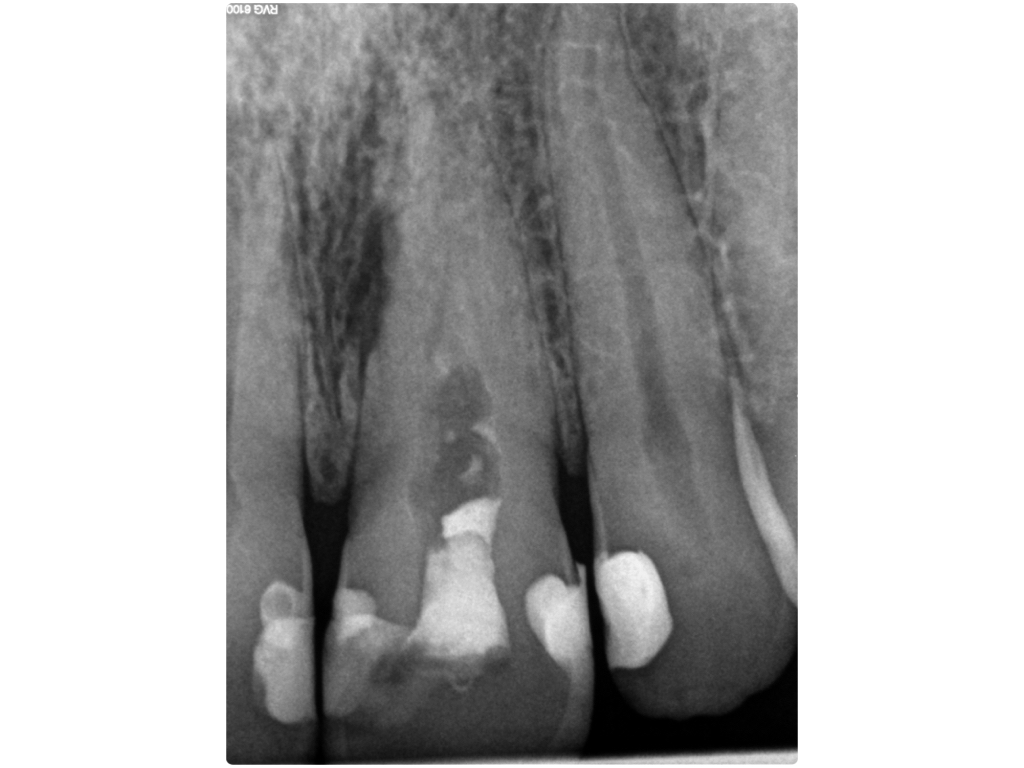

WS15_11_2.001 Veröffentlicht 17. November 2015 am 1024 × 768 in Lateraler Kanal Rö- Ausgangssituation